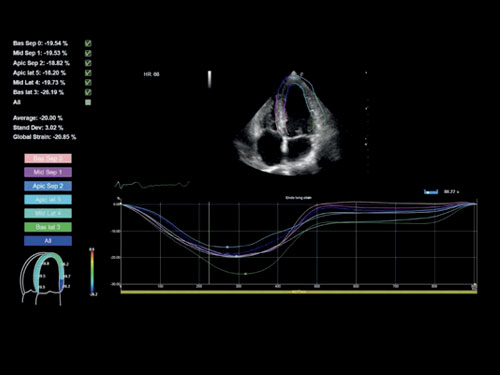

XStrain ™: Globální kmen bullseye (17 segmentů) jako výsledek 3 apikálních výsledků GLS.

XStrain4D: XStrain4D je technologie sledování, která poskytuje volumetrický model funkce srdce.